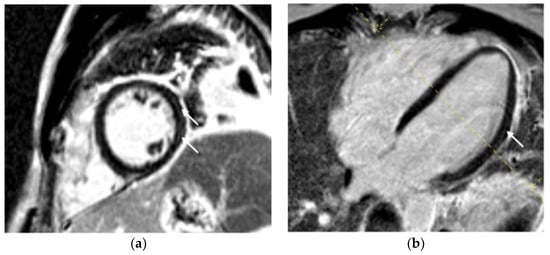

| LGE, n (%) | 67 (78.8) |

| Distribution of LGE, n (%) | |

| Subepicardial | 27 (31.8) |

| Mid-wall | 7 (8.2) |

| Transmural | 1 (1.2) |

| Subepicardial and mid-wall | 32 (37.6) |

| Late pericardial enhancement, n (%) | 34 (40.0) |

| Pericardial effusion, n (%) | 44 (51.8) |